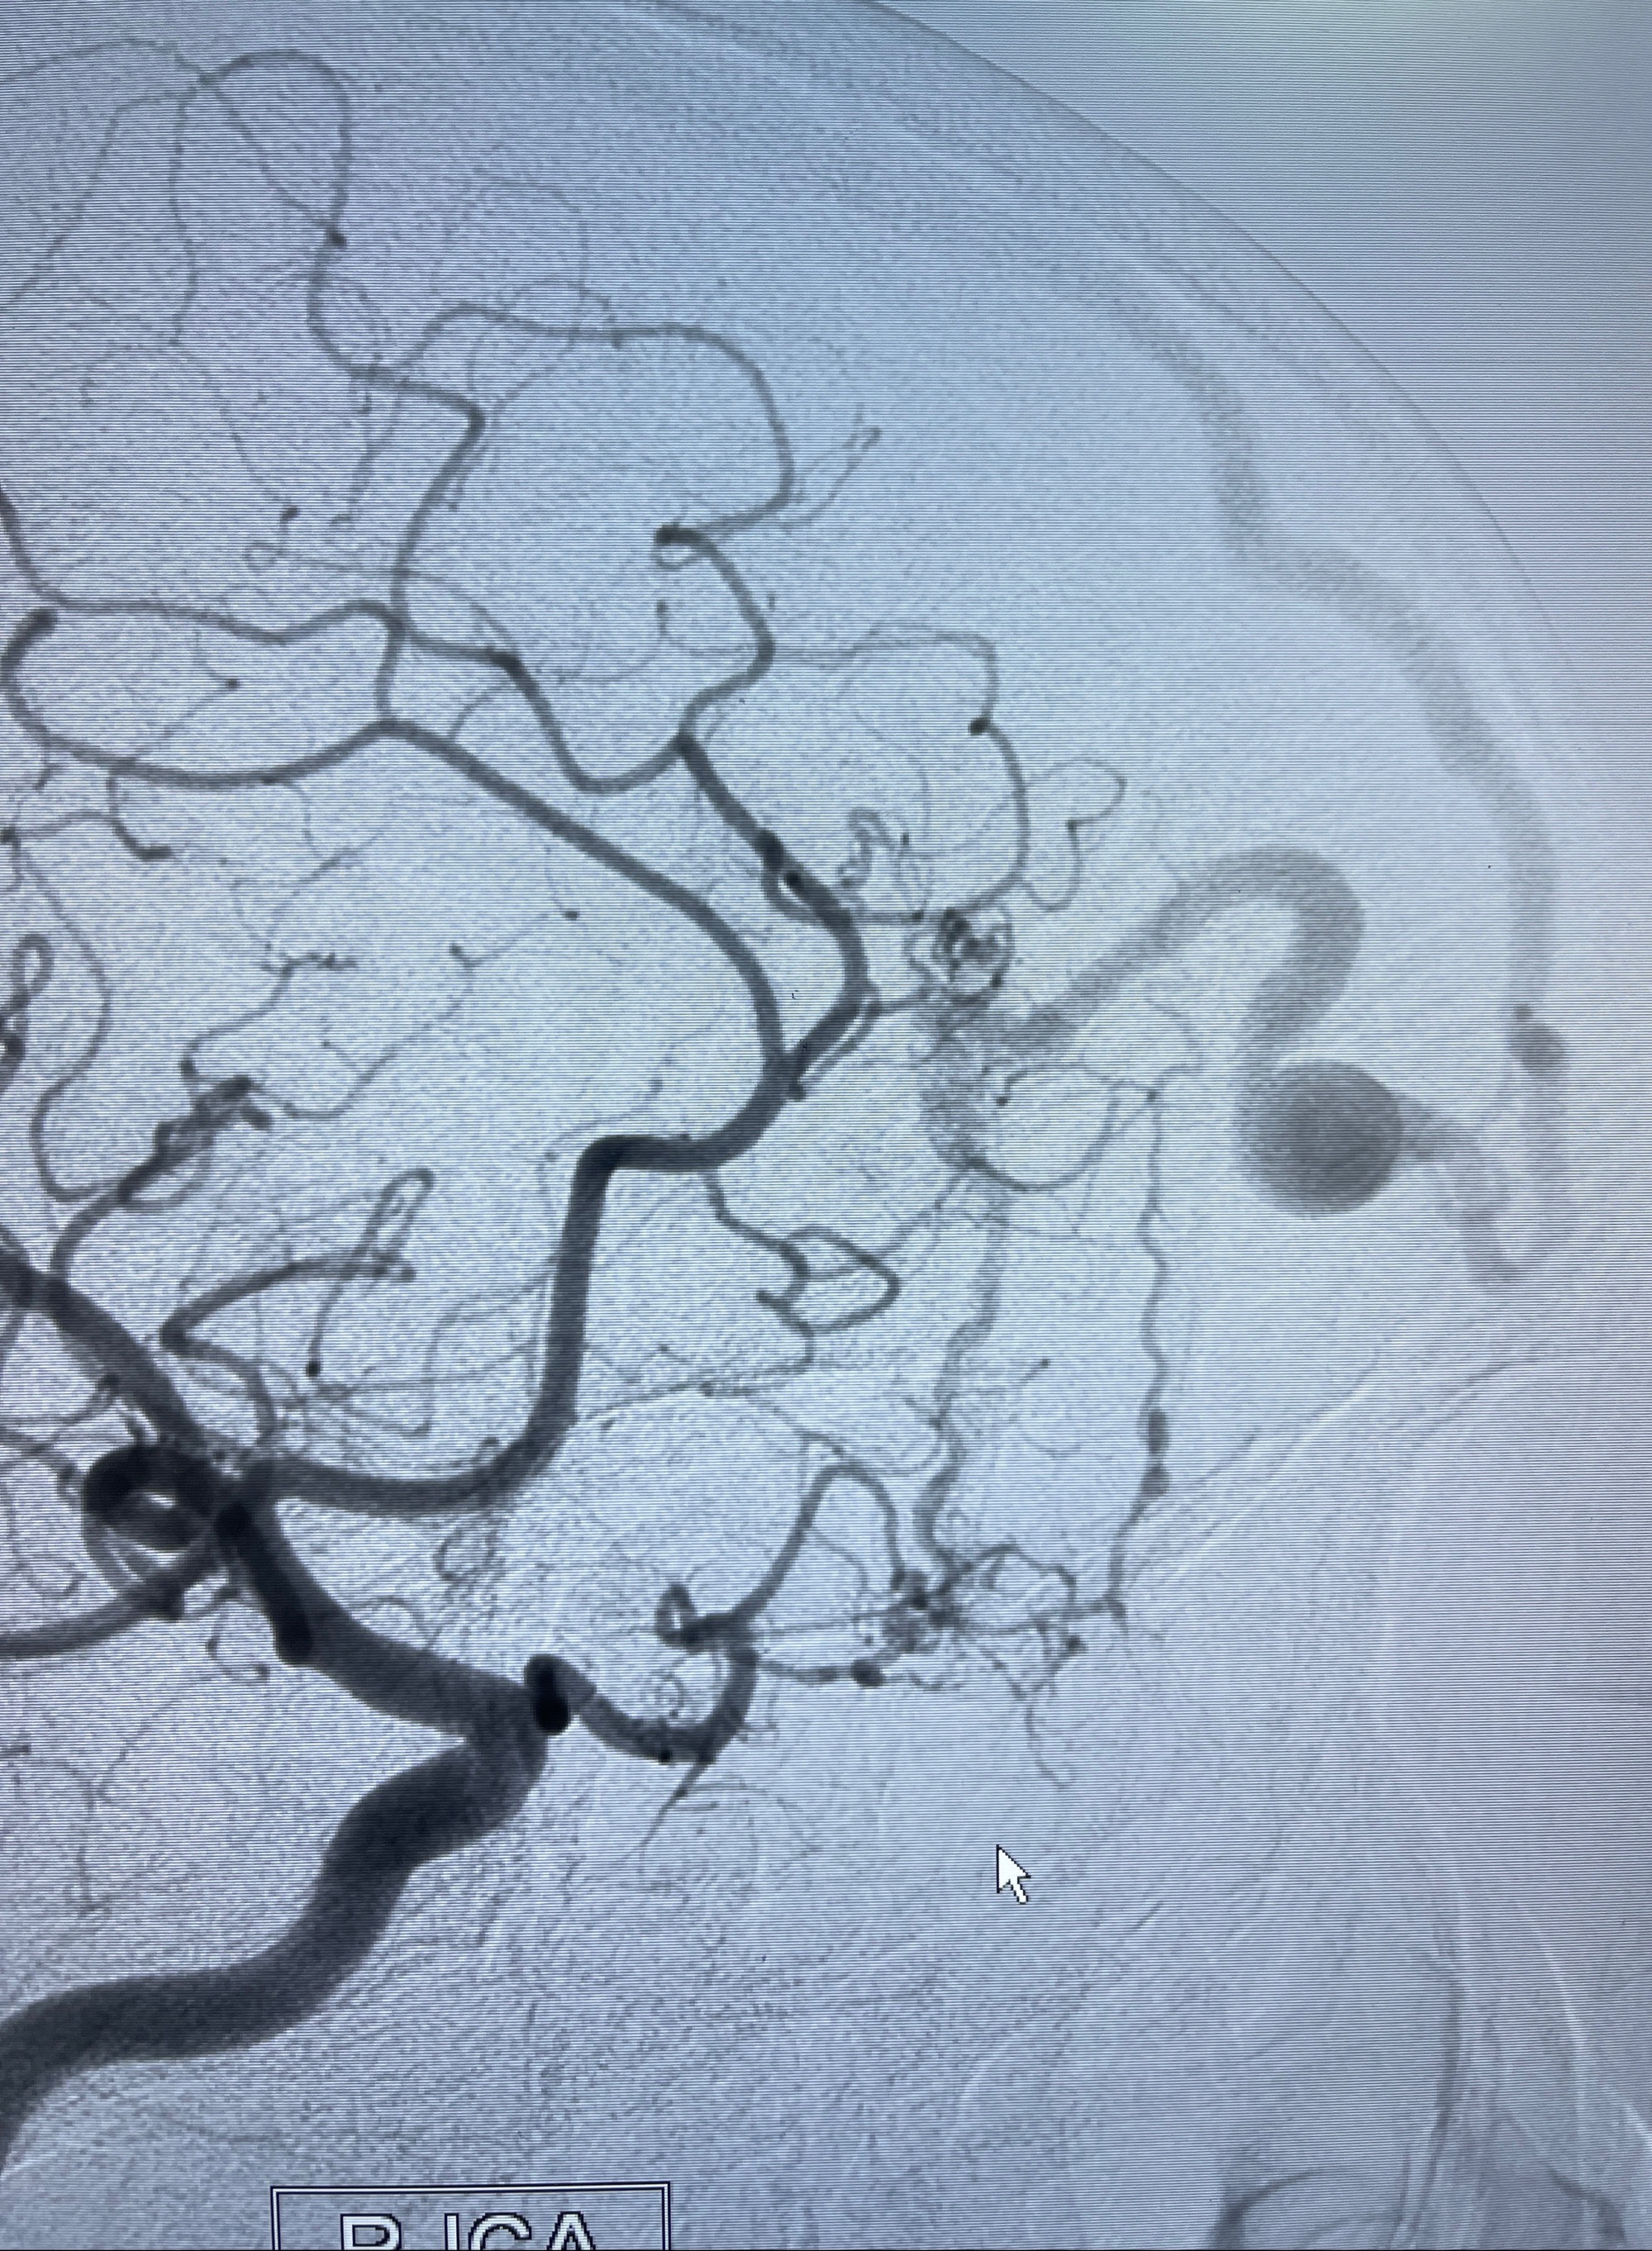

2023-09-13全脑血管造影:前颅底硬脑膜动静脉瘘,供血动脉为双侧胼周动脉、眼动脉脑膜支,静脉向上矢状窦方向引流